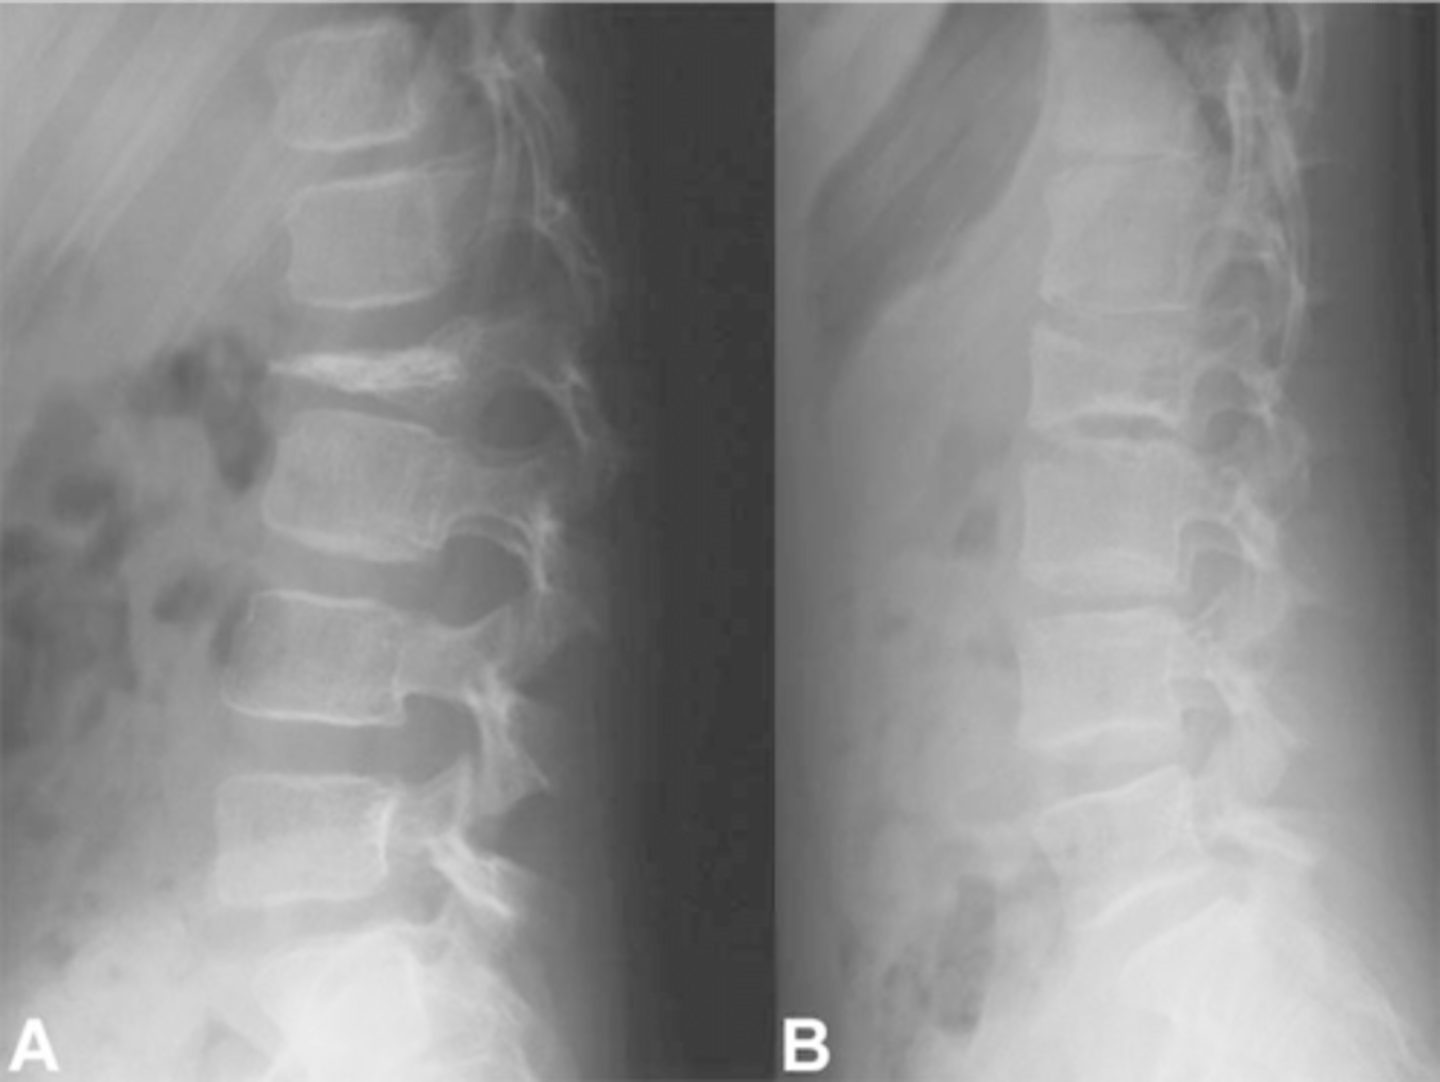

- Vertical striations (corduroy cloth)

State the radiographic features of vertebral hemangioma

Expansile

- Left: Paget Disease

- Middle: Vertebral hemangioma

- Right: Osteoporosis

Complete the DDx for vertebral hemangioma